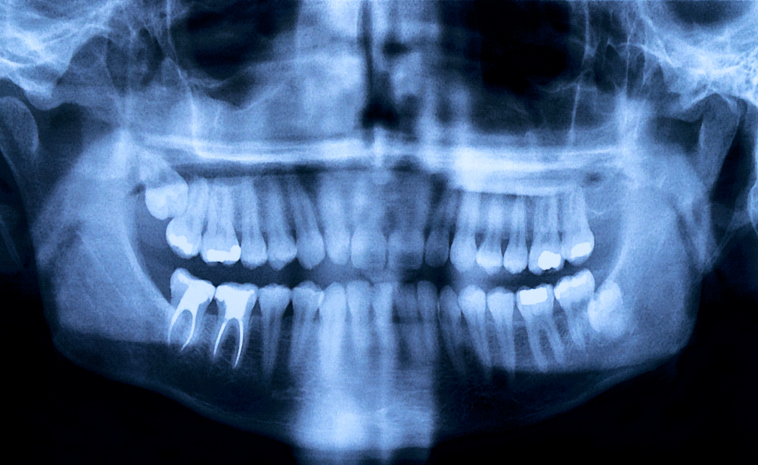

Unfortunately, there isn’t one single test that’s used to detect TMJ, but your doctor may suggest that it’s time to finally go ahead and schedule that appointment with your dentist or an ear, nose and throat specialist. A MRI is sometimes used to pick up the disorder.